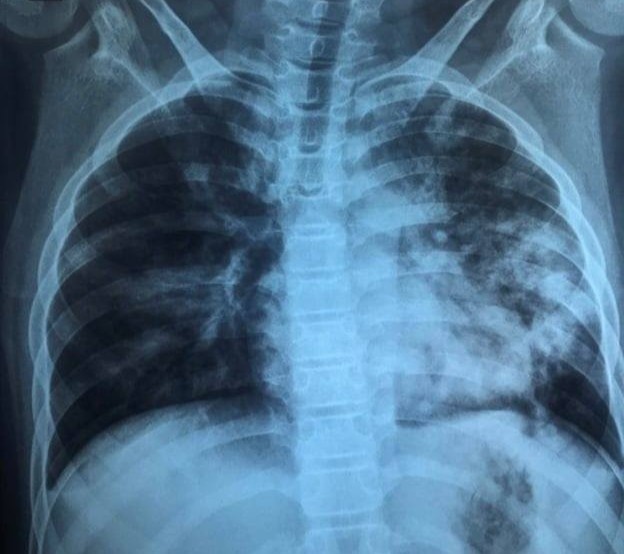

Hình ảnh X-quang của bé lúc nhập viện, phổi tổn thương nặng. Ảnh: BSCC.

Dù triệu chứng bệnh không quá rầm rộ, kết quả X-quang khiến các y bác sĩ bất ngờ bởi phổi bé bị tổn thương nặng. Ngoài ra, các kết quả xét nghiệm cho thấy phản ứng viêm tăng cao, rối loạn đông máu.